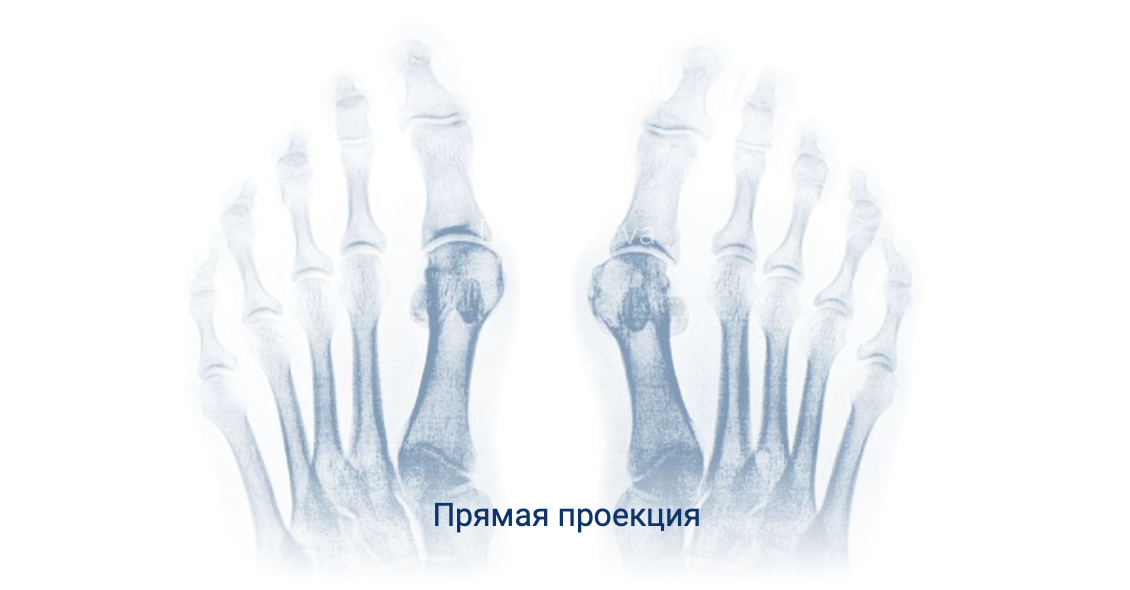

Золотым стандартом исследования при планировании хирургического лечения является рентгенография стопы в прямой и боковой проекциях с нагрузкой.

Угол отклонения большого пальца стопы более 15 градусов является диагностическим критерием патологического вальгусного отклонения. Так же в качестве дополнительных диагностических методов возможно применять МРТ, КТ, плантографию, биомеханический анализ походки и давления.